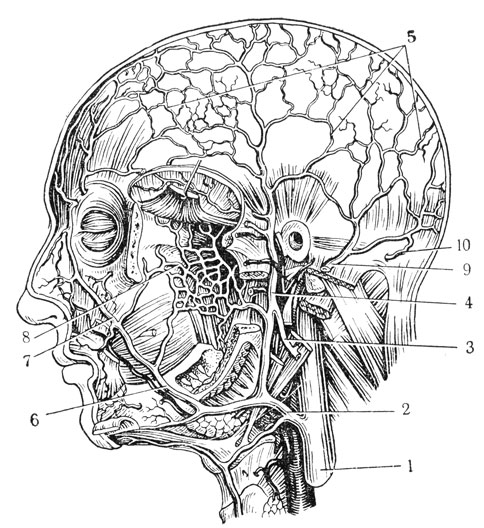

Анатомия внутренней яремной вены: КТ изображения